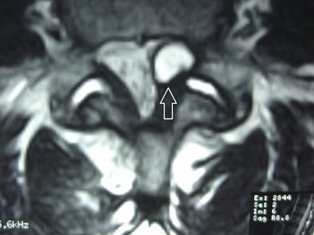

a synovial fluid-filled cyst that appears in the spine where facet joints degenerate. Synovial fluid is the lubricating fluid found in spinal joints.

Though relatively uncommon in causing spinal stenosis, the synovial cyst may cause pain, particularly in the over 65 year old patient. Synovial cysts are commonly found at the L4-5 facet joint area, causing pain into the low back, buttock, and maybe even leg. The cyst affects the spinal canal much like a disc herniation might, causing stenosis of the canal and pressure on the nerve roots.